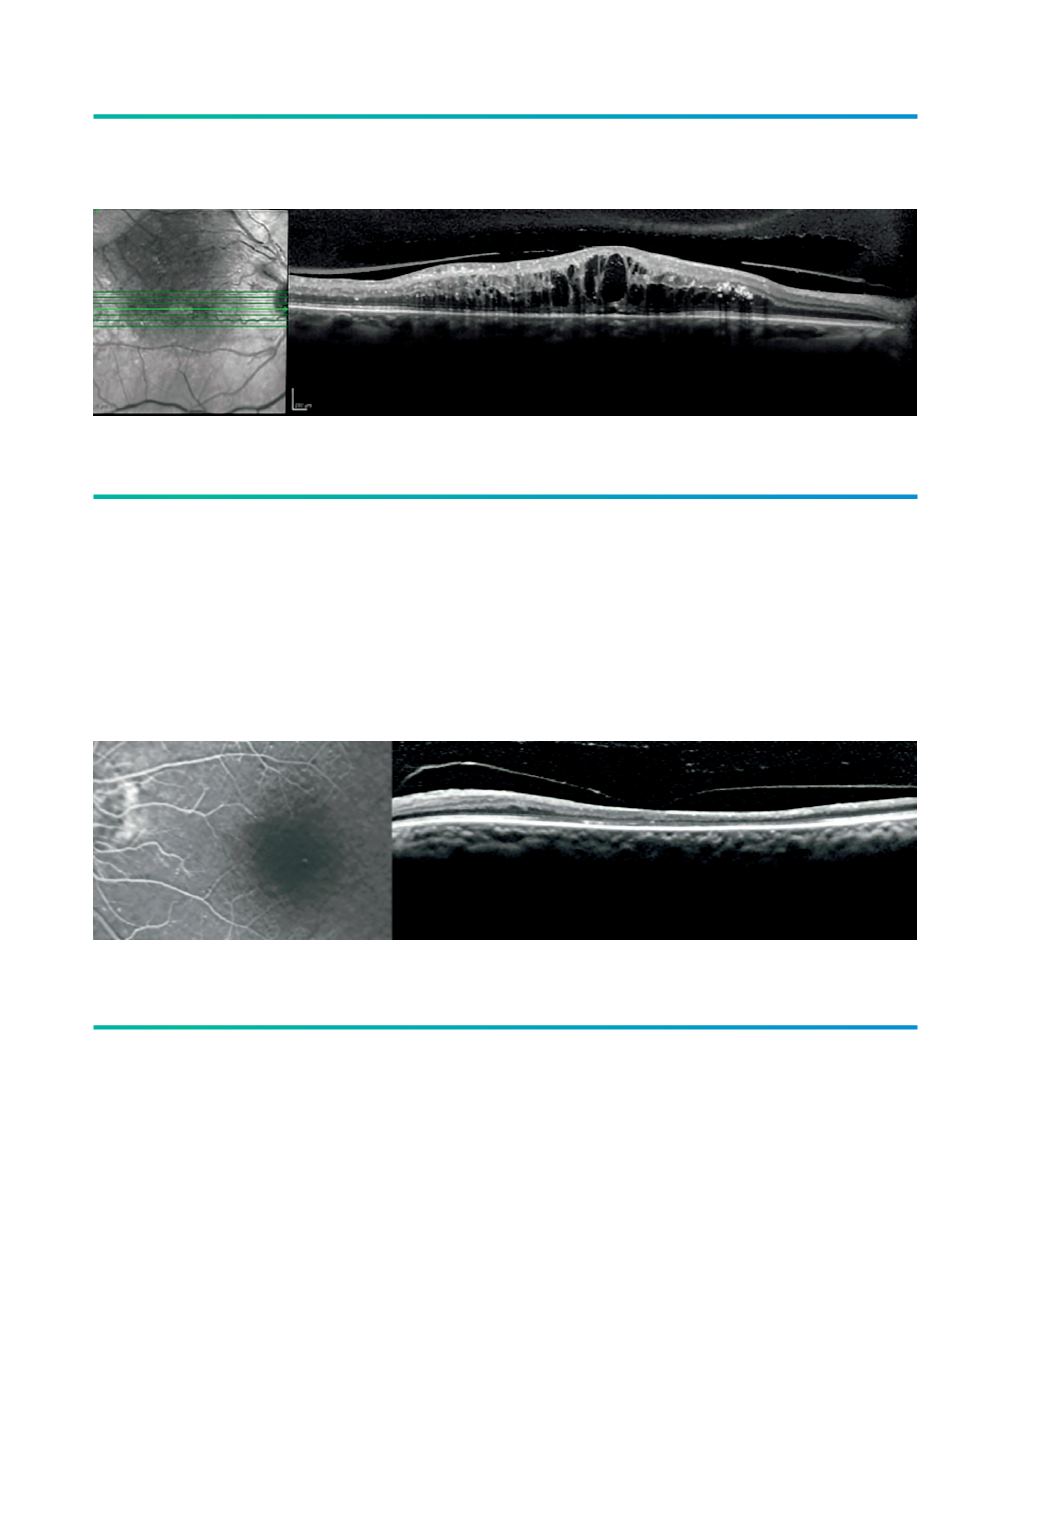

Figura 6.

AVM focal em oclusão de ramo da VCR.

Figura 7.

TVM em oclusão venosa antiga com isquemia e atrofia macular.